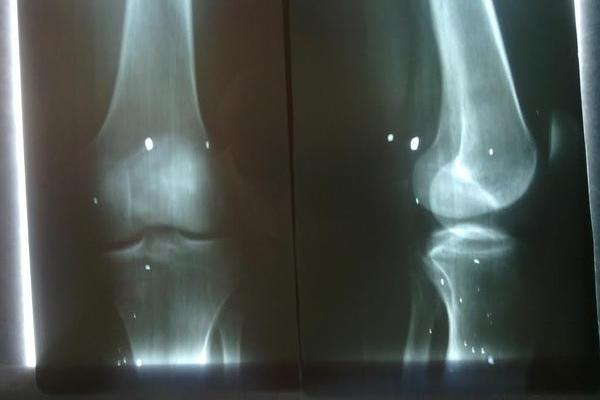

Вот рентгеновский снимок моего раненого колена, фронт и профиль. Да, эти пятнышки - это все осколки. А вот здесь, под коленом, находятся скопления нервов и артерий. И вот эти осколки должны были меня убить.

Но я даже не знал, что в колено ранен. Иначе жгут бы себе наложил. Но ничего не болело, а просто нога была занемевшей. И то, что эти разветвления артерий не зацепило - тоже чудо.